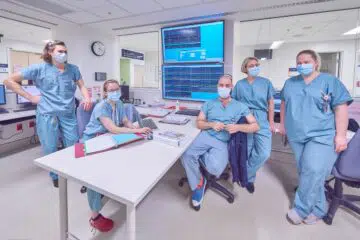

L’infirmier est un agent de santé qui peut travailler dans plusieurs secteurs de la médecine. Entre autres domaines où vous pourrez le retrouver, il y a par exemple la chirurgie, la gériatrie, le bloc opératoire et beaucoup d’autres. Néanmoins, la sage-femme a pour principale mission de faire accoucher et d’assister l’infirmier. Quel est le rôle […]